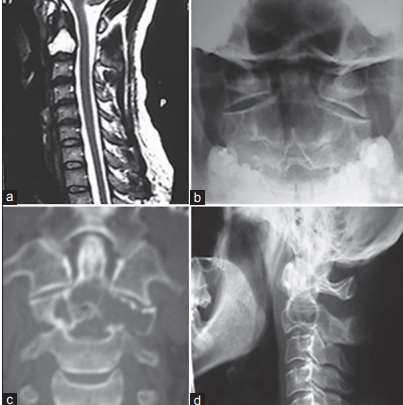

Cistos degenerativos intraósseos(CDI) da espinha cervical são raros. CDIs dentro de C2 foram reportados em apenas 3 artigos. Nós ilustramos um paciente com dor no pescoço devido a um CDI dentro da segunda vértebra. Discutimos o diagnóstico diferencial das lesões e as abordagens cirúrgicas para alcançar essa região anatômica complexa.

Por Dr. Gustavo Rassier Isolan, MD PhD.